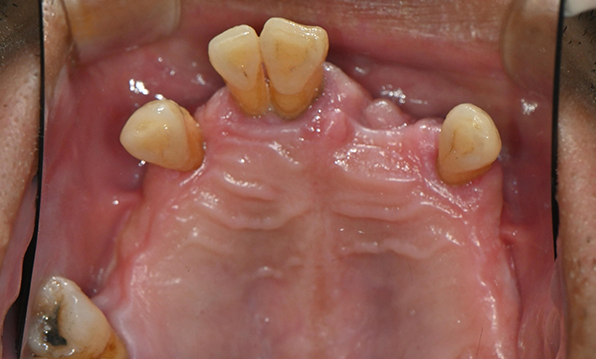

Before & After

| Before | After |